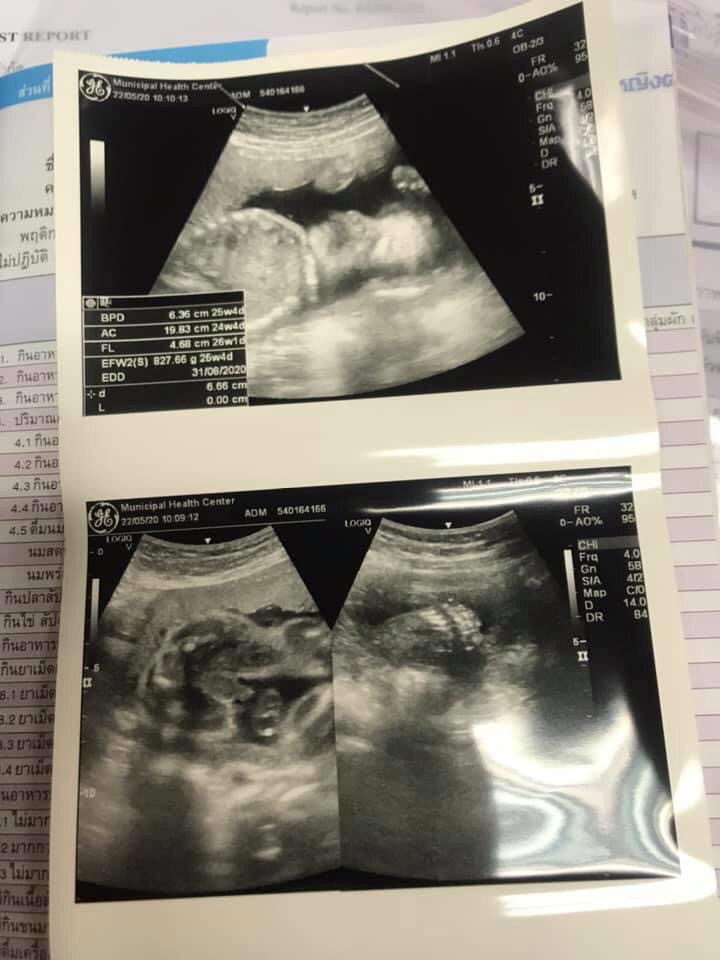

กำหนดคลอด 30 สิงหาฯ ค่ะ😊 ผช ครับ ตอนนี้ยังไม่รู้นำหนักลูกที ภาพตอนซาวน์ 26 สัปดาห์

29w 0dน้ำหนัก 1,180 กรัม กำหนดคลอด 21 สิงหา. ผู้หญิงค่ะแม่(ภาพตอน24w0dนะคะ)